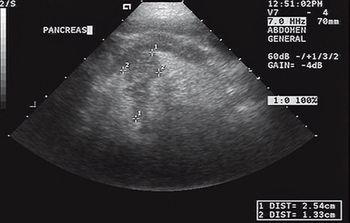

A 15-year-old 15.1-lb (6.9-kg) castrated male Lhasa Apso was presented to the Veterinary Medical Teaching Hospital at Texas A&M University for evaluation of chronic vomiting of several months' duration.

Hypertensive encephalopathy (HyE) is an acute neurological syndrome, which can be characterized by any of the following clinical signs: nausea, vomiting, abnormal vocalization, ataxia, tremors, photophobia, blindness, frequent blinking, head pressing, stupor and/or seizure activity.